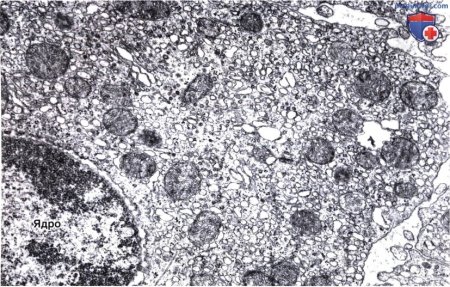

Микрофотография клетки печени животного - захватывающий снимок, который открывает перед нами мир мельчайших структур организма. Эта клетка, являющаяся основным строительным блоком печени, обладает удивительными функциями и способностью регенерации. На фото можно ясно увидеть ее уникальную структуру, включая ядро, мембраны и различные органеллы. Изучение таких микромира помогает нам лучше понять работу организма в целом и разрабатывать новые методы лечения и диагностики различных заболеваний.

на рисунке представлена микрофотография клетки печени животного для срисовки